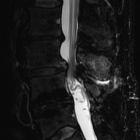

MRI

May demonstrate interspinous bursal fluid and posterocentral epidural cyst(s). MRI can be very helpful in determining whether there is resulting posterior compression of the thecal sac.